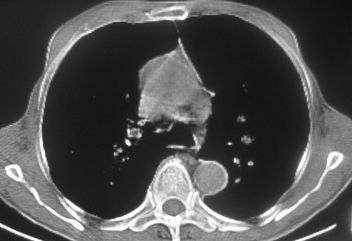

以下是引用卜一在2007-10-7 9:38:00的发言:[br]左下肺胸膜下团片影,内见含气支气管像,临近胸膜未见增厚。多考虑:1 左下肺炎症,建议消炎后复查!2 不除外肺隔离症合并感染!